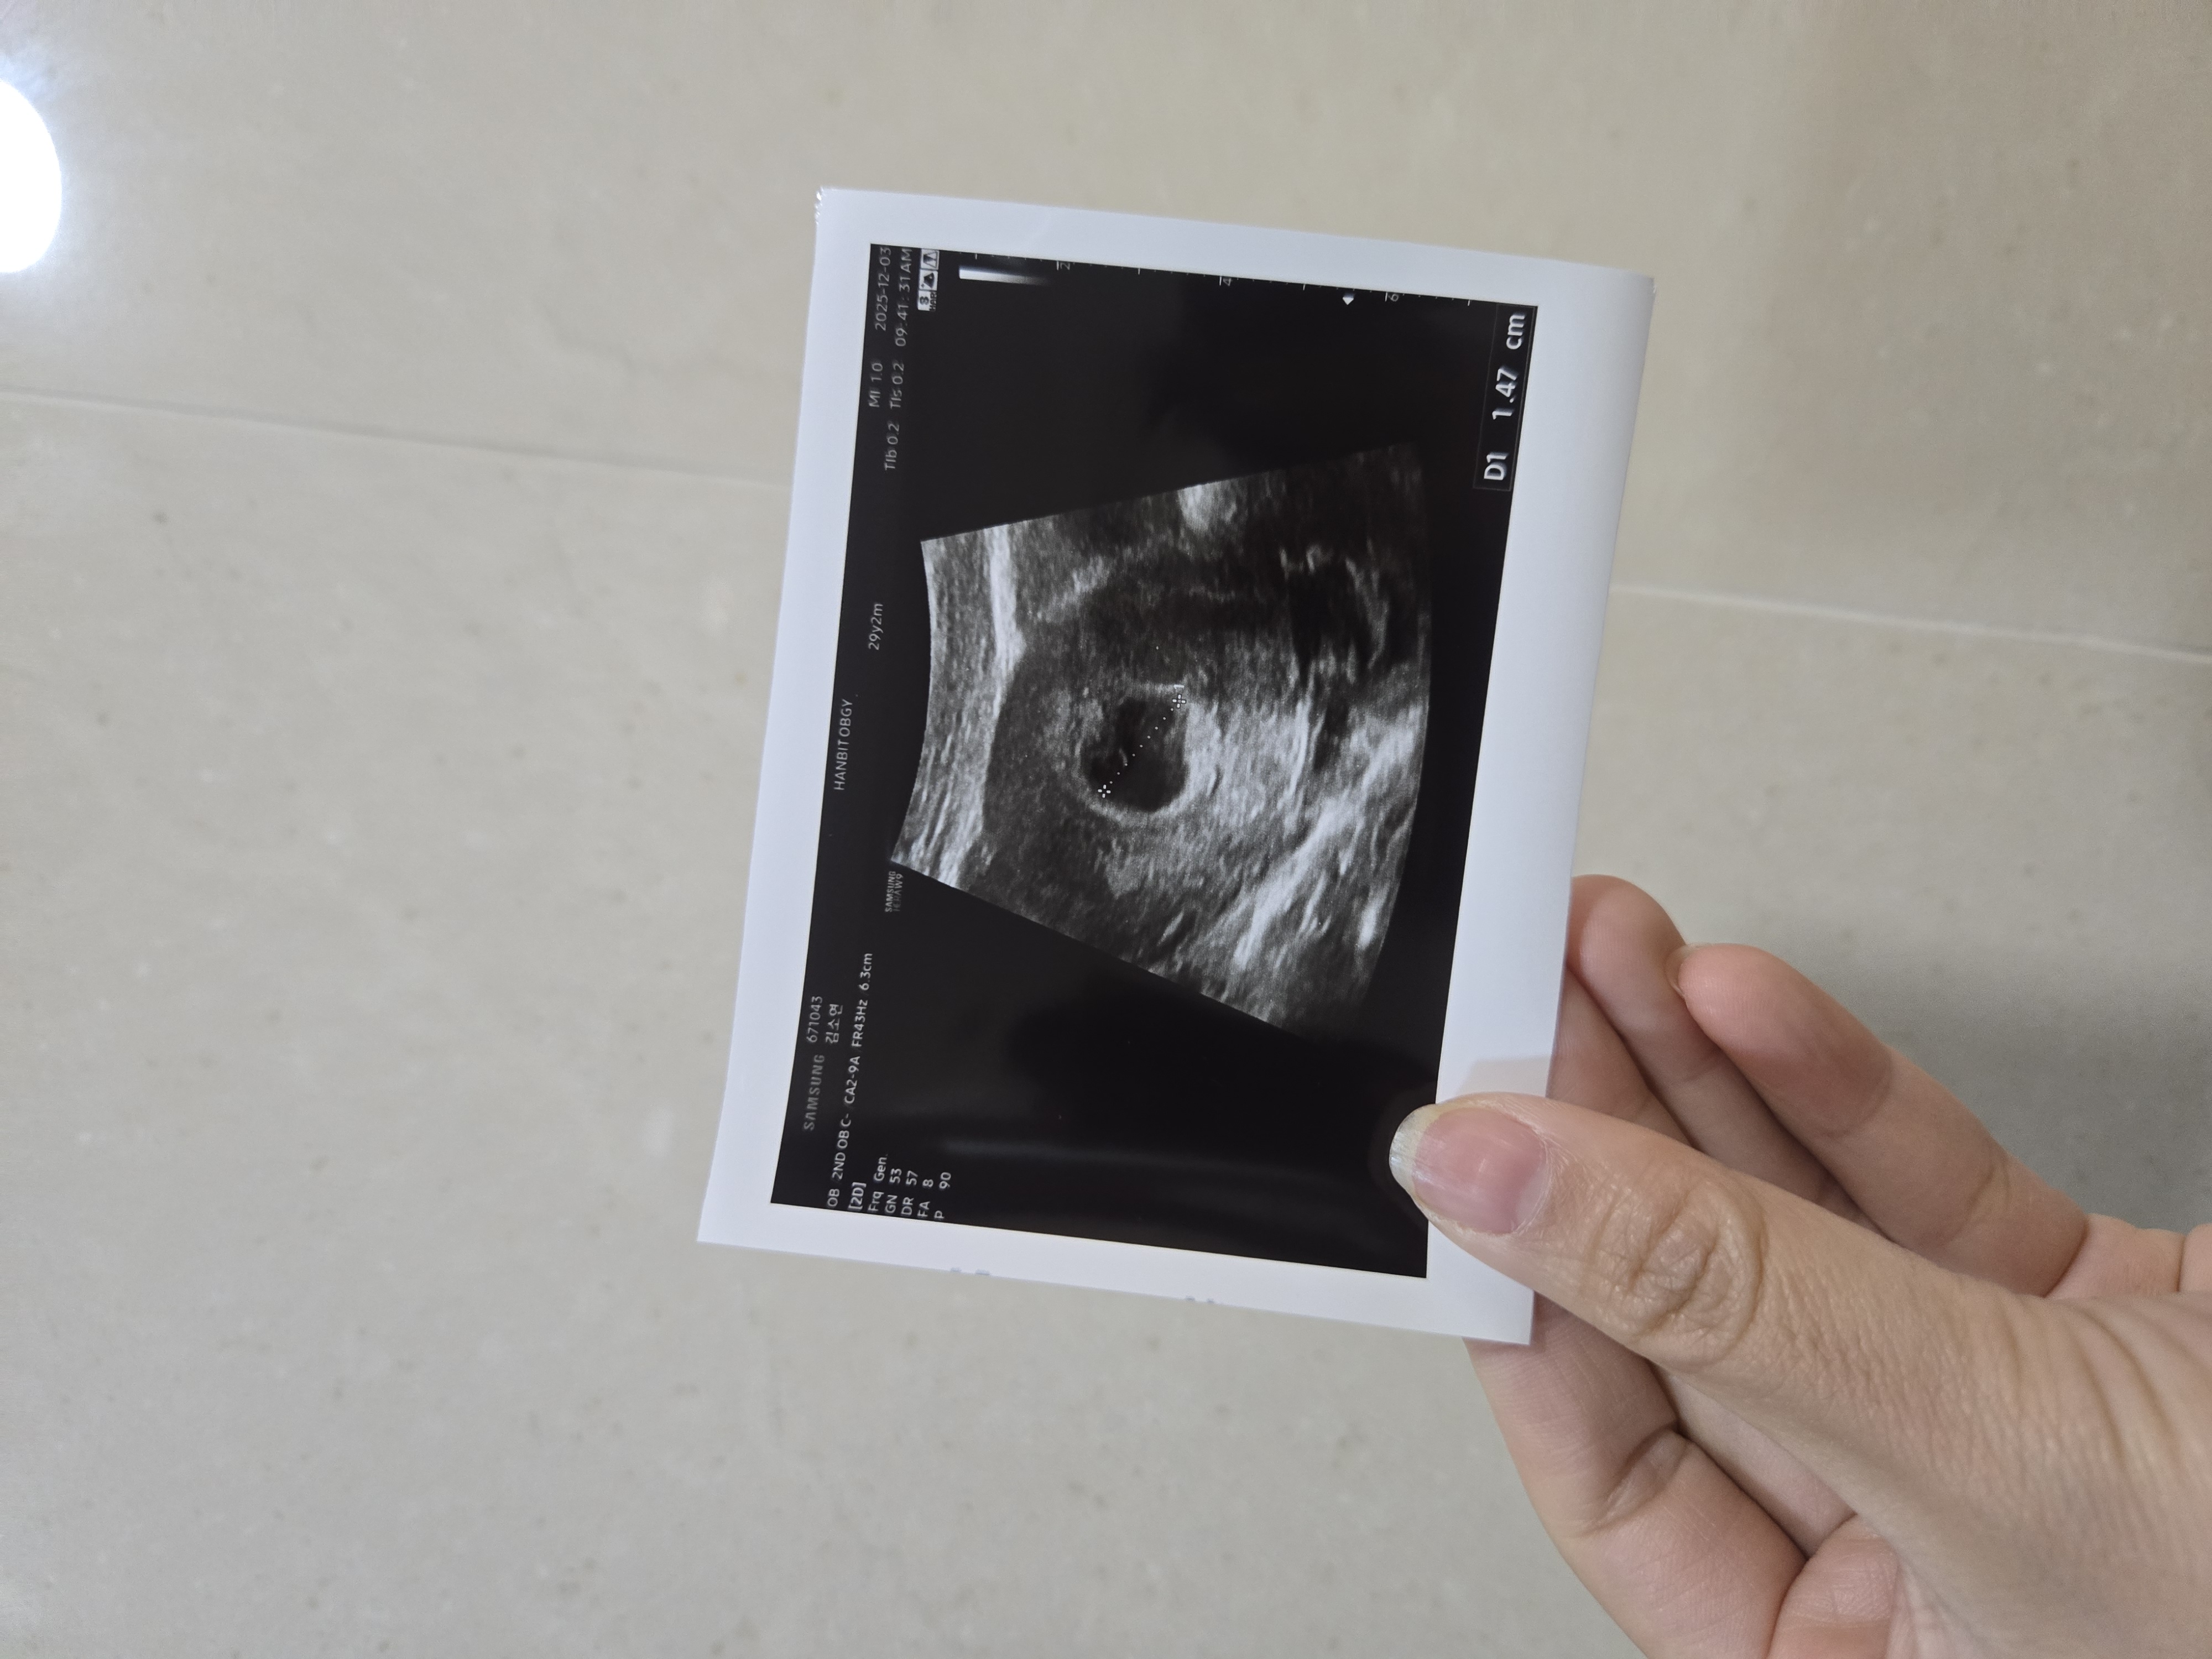

드디어 아기집 봤어요 !!!!

저번달 화유하고 이번달에 아기가 바로 찾아와줬어요 ! 저번에는 아기집도 못보고 끝나서 이번에는 아기집 보기까지 너무 떨렸는데, 6주 0일차 ! 드디어 봤네요 ㅠ 보자마자 눈물 난 ㅜ.ㅜ 아기집 모양도 동그랗고 난황까지 보고왔어요 다음주면 심소 들을 수 있을거 같다네요 무럭 무럭 잘 커주길 바래봅니다 !